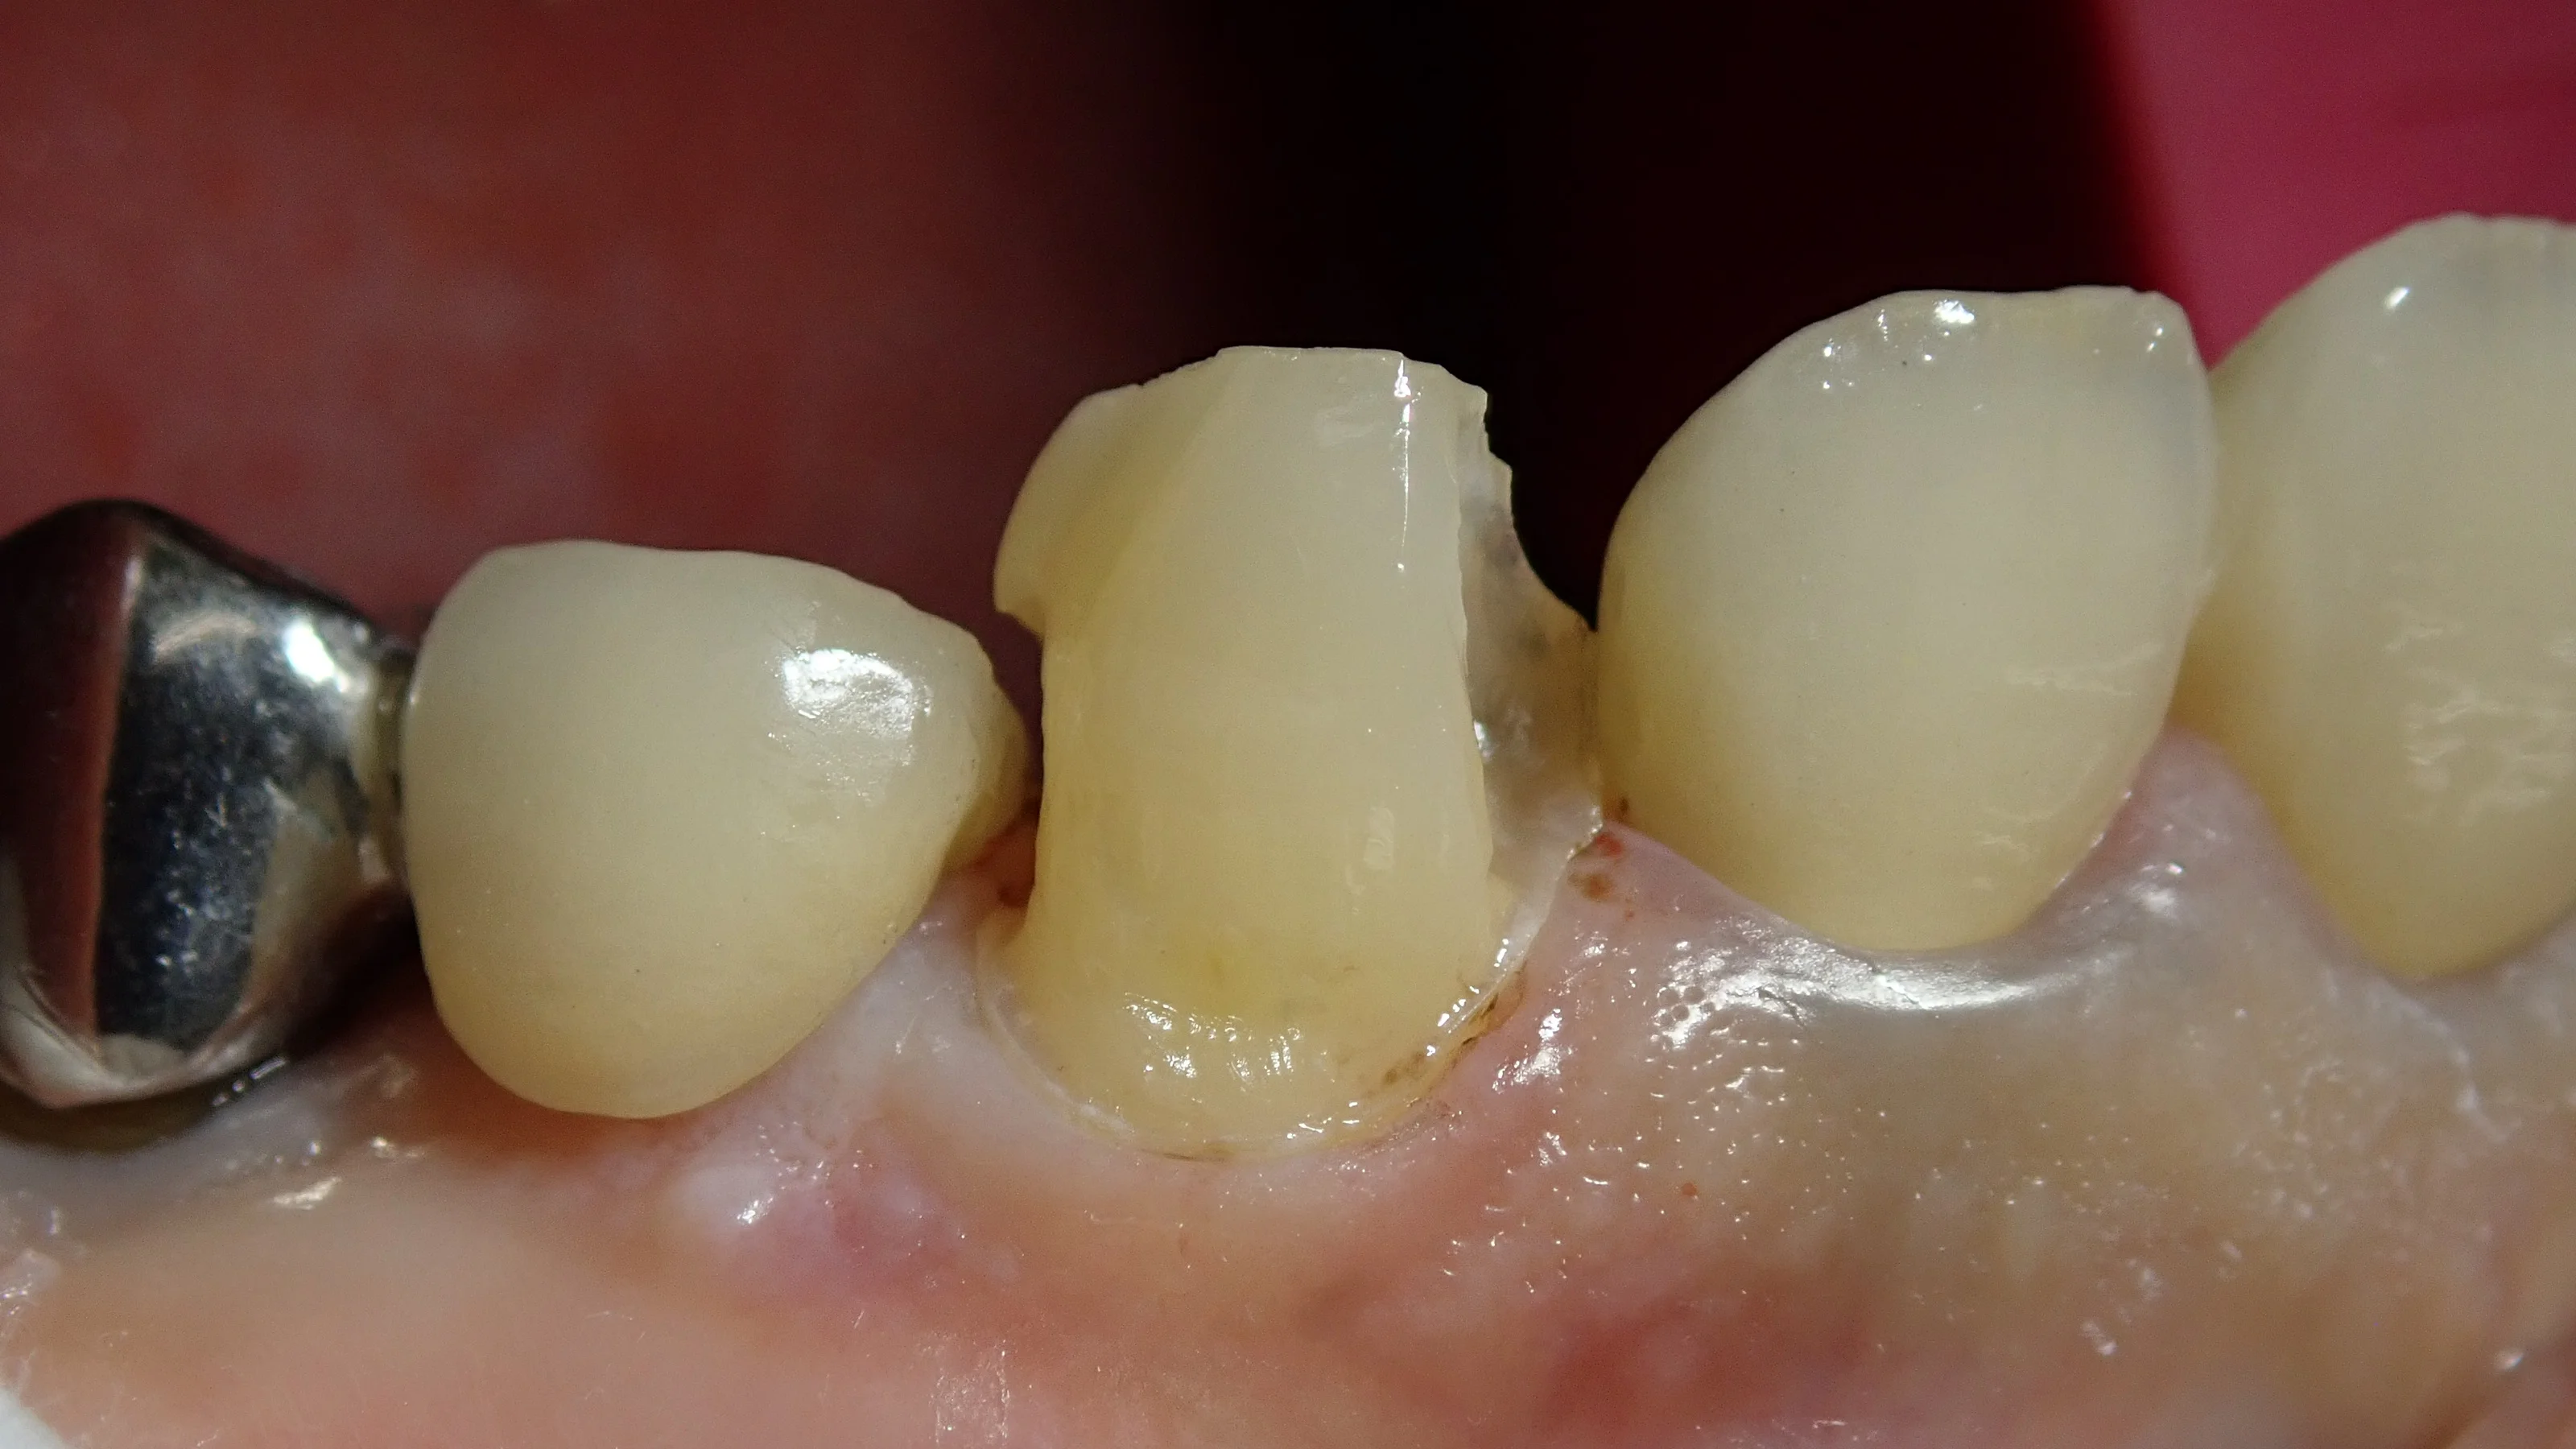

画面中央の歯が、今回処置を行った歯ですが、

既に結構広い範囲で保険適用材料である「コンポジットレジン」にて充填されてあります。

ただ、あからさまに中が黒くなってしまっているのが分かると思います。

裏の方にも薄く広く詰められてしまっていますので、先生によってはクラウンを選択されてしまうケースかと思います。

で、こちらが虫歯とコンポジットレジンを取りきった状態です。

影の感じで分かるかもしれませんが、前後の歯の間が非常に深い虫歯になってしまっていました。

ただ、幸い歯を上手いこと温存出来ました。

もう少し大事な部分の歯が無くなってしまっていたら、治療方針を変更してクラウンを視野に入れることになりそうでした。